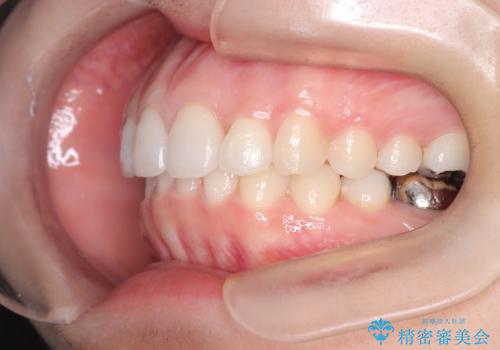

【インビザライン】前歯を引っ込めたい

- 前歯が出ていることを主訴に来院された患者様です。

抜歯を希望されなかっため、臼歯部の遠心移動やIPRを行い配列を行っています。

抜歯をしていない矯正となるため、口元に大きな変化は認められません。